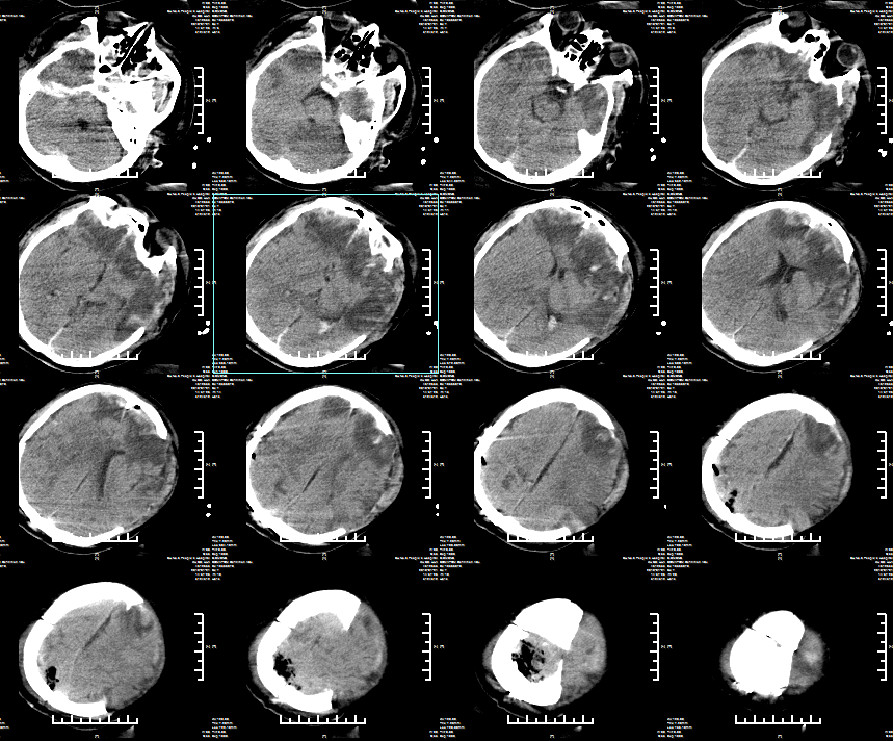

最适脑灌注压(CPP)治疗术后第二天24小时

通过将该患者CPP控制在根据第二个4小时计算出的最适CPP水平(65-75mmHg)。患者实际CPP在65-75mmHg 占比达83.1%,PRX>0.25占比24.1%。回顾分析患者术后第二天24小时监测数据,PRx与CPP呈明显的U型关系,该患者最适CPP在65-75mmHg之间。继续最适CPP治疗。

2019年2月12日患者出院头颅CT

查体:GCS评分:4-1-4=9分,双瞳孔等圆等大,直径约2.0mm,对光反射存在。病理征阴性。转康复医院继续治疗。